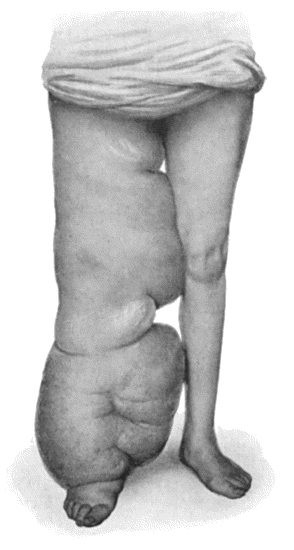

358 89.Elephantiasis Neuromatosa in a woman æt. 28